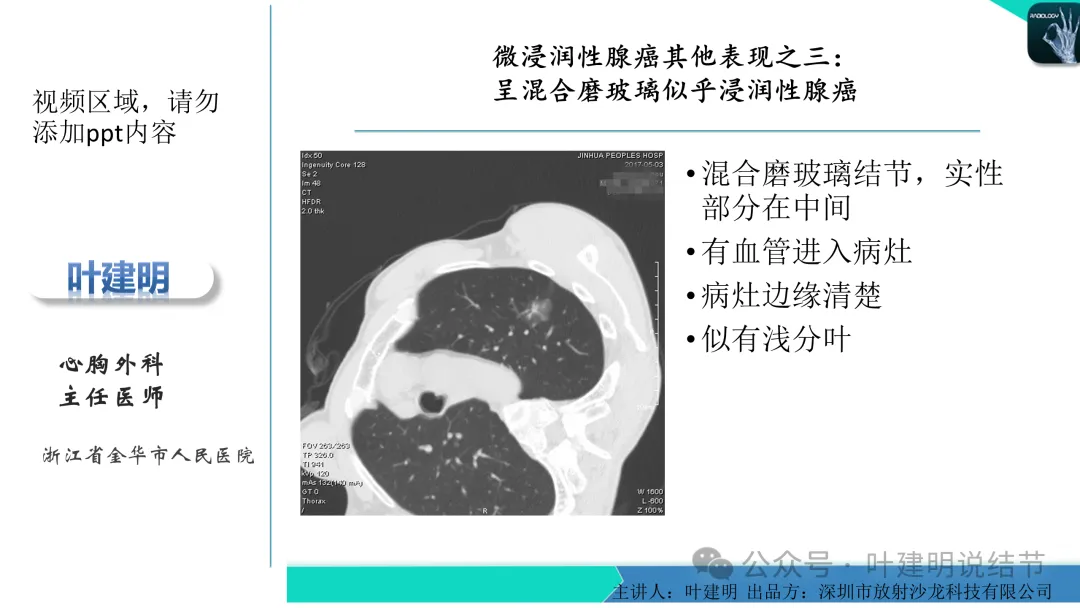

早在2020年时,我受邀在《放射沙龙》做过一个系列的精品课,当时专门总结分析过各类良恶性肺结节与肿块的影像特征,这是当时关于微浸润性腺癌影像特征的分析,今天看来仍基本不太需要改变,大家有兴趣的可以参考: